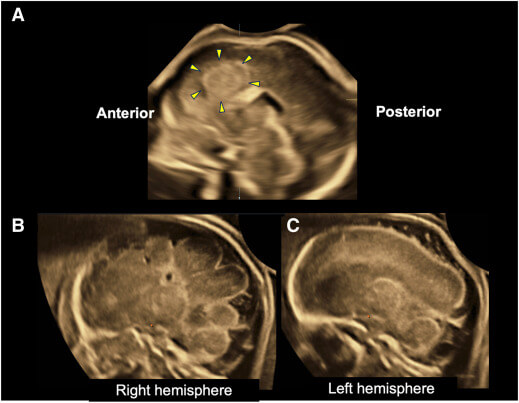

28歳・初産婦、妊娠19週6日。 正中線のズレ(Aの図)が見つかり、経腟超音波で脳梁のあるはずの場所に腫瘍様の塊(病理で過誤腫と判明)、右半球の回転の乱れ(Bの図)、左は週数相当の平滑表面(Cの図)を確認。胎児の羊水+ご両親の血液で解析するトリオエクソームは病的変異が見つかりませんでした。

剖検では、男児の右の脳が左より小さく、右帯状回に過誤腫を認め、右半球内側で脳の溝が深くなる異常(皮質形成異常)が見られました。さらに、病変の細胞だけを詳しく調べると、特定の遺伝子(OFD1)に起きた変化がその場所にだけ存在しており(=体細胞モザイク、割合は約22%)、他の脳の部分や羊水、両親の検体には認められませんでした。このことは、受精後に脳の一部だけで起きた局所的な変化が原因であり、全身に共通して起きるタイプの変化(生殖細胞系列)ではないことを示します。このOFD1遺伝子はX染色体上に位置しており、全身に同じ変化がある場合は男児では致死的で初期流産が必発となりますが、今回は局所の変異だったため妊娠中期まで順調に発育し得たと考えられ、次の妊娠で同じことが起こる可能性はほぼないと説明できます。